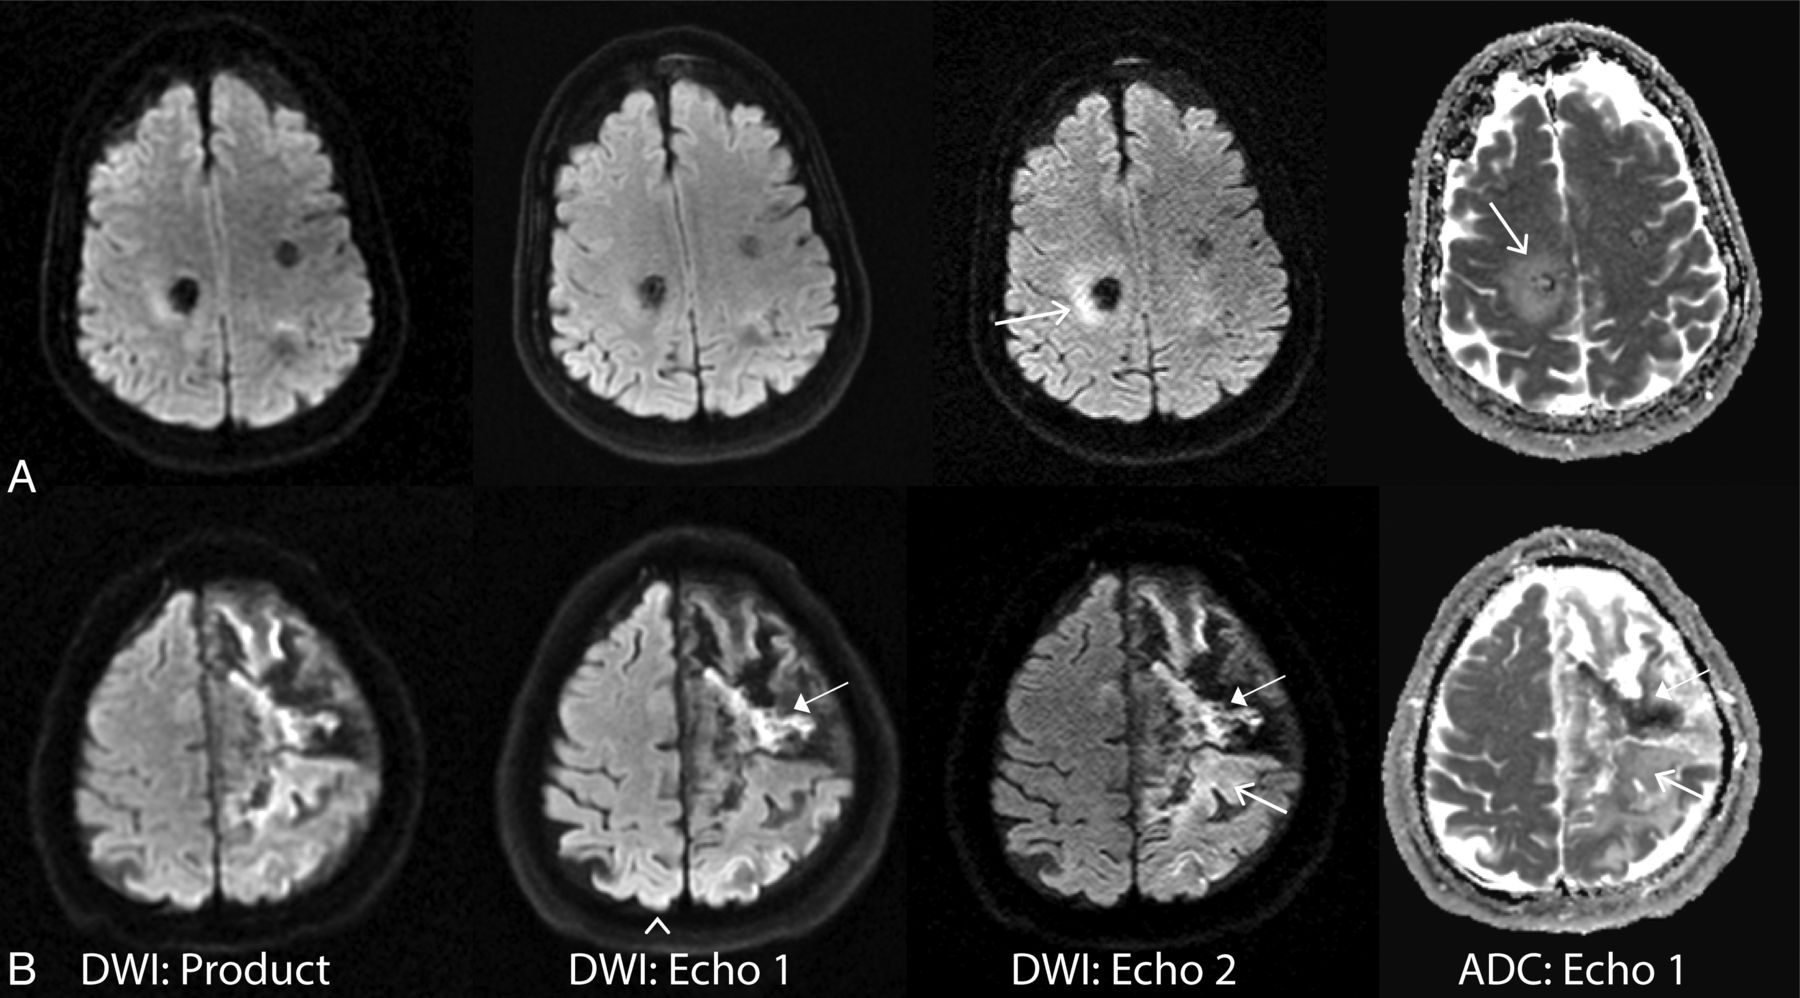

Figure 4 depicts 2 cases in which echo 2 demonstrates improved lesion conspicuity compared with echo 1. These patients had recently undergone surgery, and the findings on echo 2—while not likely to alter clinical management as determined during the radiologists' readings—better defined the nature of the postoperative changes (such as local ischemia and/or hemorrhage), potentially revealing etiologies for perioperative symptoms.

Examples of improved lesion detection of echo 2. A, A 56-year-old man status post posterior fossa tumor resection. Right cerebellar injury is more conspicuous on echo 2 and was confirmed to have reduced diffusion based on ADC. B, A 39-year-old man with known Moyamoya disease status post right superficial temporal artery to middle cerebral artery anastomosis presented with acute strokelike symptoms. Superficial temporal cortical lesion (closed arrow) and a punctate putaminal lesion (arrowhead) are confirmed with reduced diffusivity based on the ADC map. Also note improved delineation of a small subdural hematoma on echo 2 (open arrow).